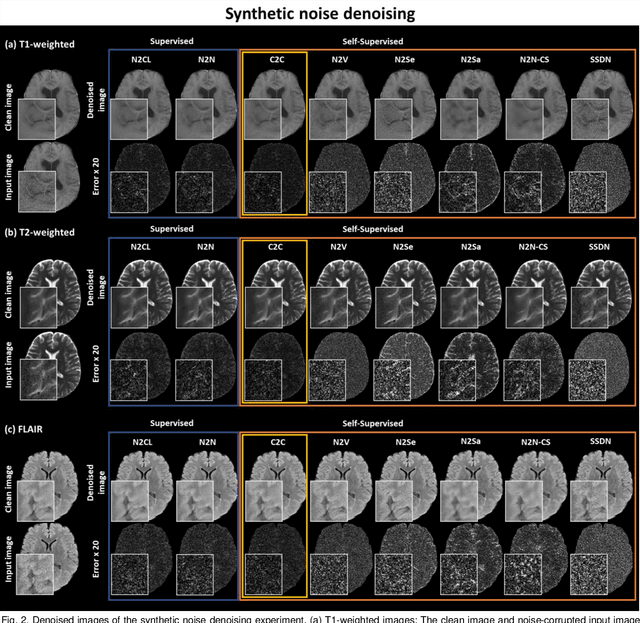

Abstract:Denoising of magnetic resonance images is beneficial in improving the quality of low signal-to-noise ratio images. Recently, denoising using deep neural networks has demonstrated promising results. Most of these networks, however, utilize supervised learning, which requires large training images of noise-corrupted and clean image pairs. Obtaining training images, particularly clean images, is expensive and time-consuming. Hence, methods such as Noise2Noise (N2N) that require only pairs of noise-corrupted images have been developed to reduce the burden of obtaining training datasets. In this study, we propose a new self-supervised denoising method, Coil2Coil (C2C), that does not require the acquisition of clean images or paired noise-corrupted images for training. Instead, the method utilizes multichannel data from phased-array coils to generate training images. First, it divides and combines multichannel coil images into two images, one for input and the other for label. Then, they are processed to impose noise independence and sensitivity normalization such that they can be used for the training images of N2N. For inference, the method inputs a coil-combined image (e.g., DICOM image), enabling a wide application of the method. When evaluated using synthetic noise-added images, C2C shows the best performance against several self-supervised methods, reporting comparable outcomes to supervised methods. When testing the DICOM images, C2C successfully denoised real noise without showing structure-dependent residuals in the error maps. Because of the significant advantage of not requiring additional scans for clean or paired images, the method can be easily utilized for various clinical applications.